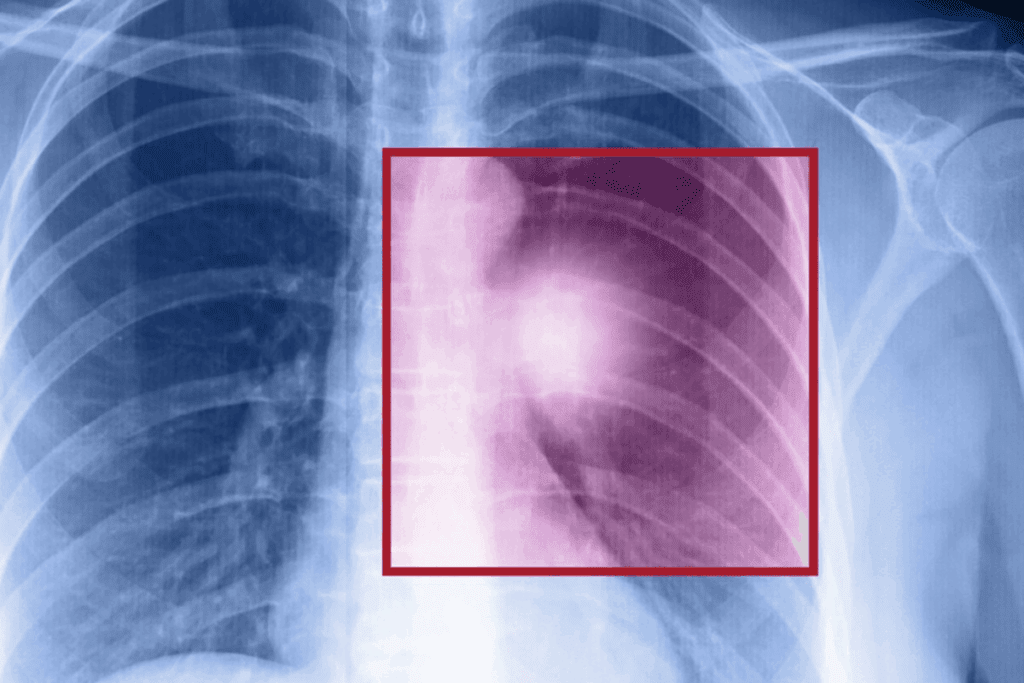

Going through lung surgery can be scary, and many wonder about the surgery itself. A big question is if ribs get broken during it.

About 30% of lung surgeries use a thoracotomy incision. This is when the chest is opened to reach the lungs. We’ll look at the different lung surgery techniques, from the old ways to the new, less invasive ones.

Where Do Most Lung Cancers Start? Understanding Lung Cancer OriginWe aim to give a clear picture of what happens during lung surgery, especially addressing concerns about ribs broken for lung surgery. We’ll focus on how surgeons try to avoid hurting the rib cage during the procedure.

The idea that ribs are always broken during lung surgery is not true. Lung surgery, or thoracic surgery, includes many procedures. These may need different ways to open the chest.